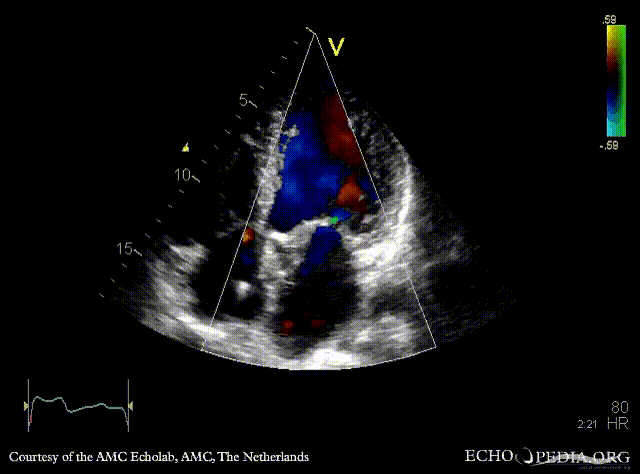

E00844.gif E00845.gif

PLAX: abscess of aortic valve prosthesis PLAX with Color Doppler: severe mitral regurgitation